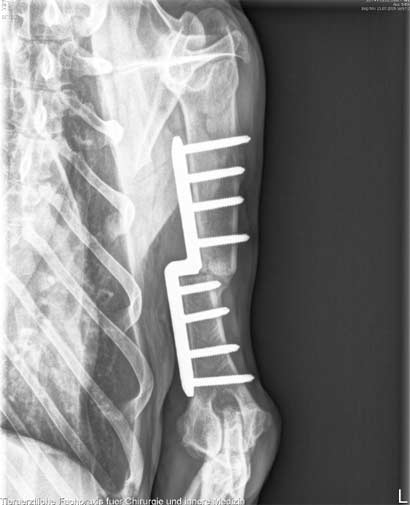

Cara´s OP am Ellenbogengelenk ist gut verlaufen..

Es wurde eine SHO vorgenommen, damit der sehr stark beschädigte innere Kniegelenksanteil entlastet wird.

Wir freuen und riesig für das Mädchen, dass sie in ein paar Wochen, wenn Ihre strikte Ruhephase vorbei ist, endlich ihre so sehr geliebten Spaziergänge ohne Schmerzen genießen kann! |